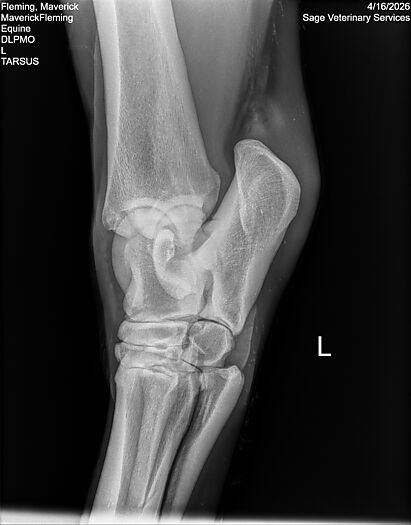

**Maverick sells at the Colorado Horse Sale’s Best of the West Select Sale on May 30th in Castle Rock, CO - He will complete the riding & handling Sift Exam, baseline veterinary exam, and will sell with 4 total radiographs (DLPMO & Front Foot Lateral)**